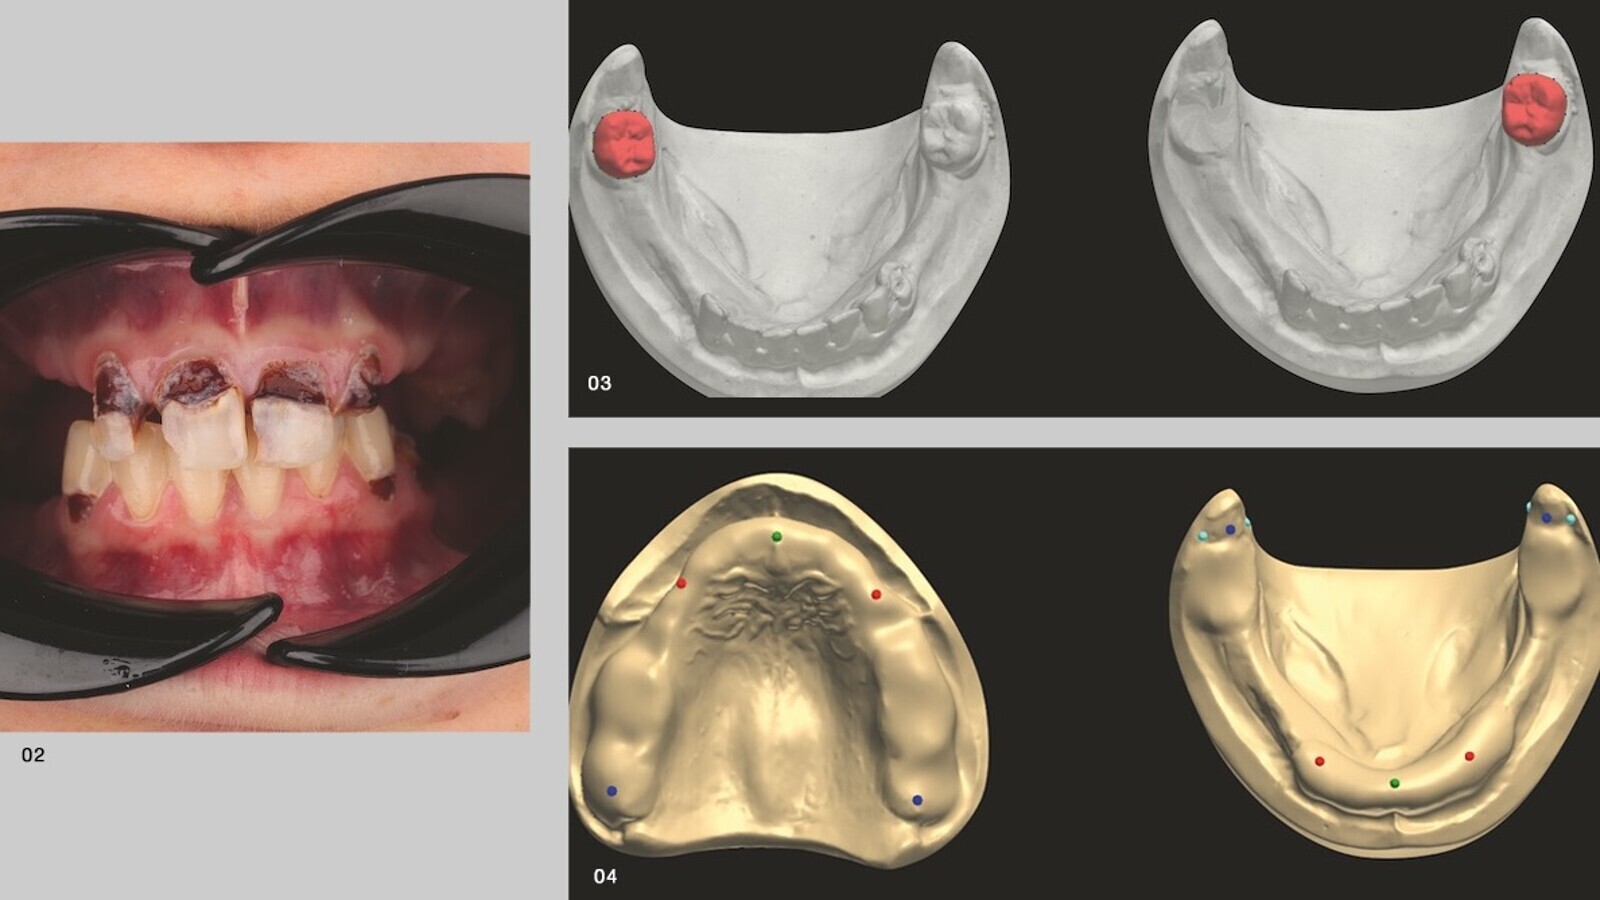

Fig. 2. Daño masivo en los dientes restantes. Fig. 3. Extracción virtual de los dientes restantes en el software. Fig. 4. Análisis de modelo virtual.

Para la construcción de las prótesis provisionales, los dientes restantes tuvieron que ser borrados en los modelos virtuales (Fig. 3). Para esto, en el software se dispone de las herramientas correspondientes. Durante el análisis del modelo, el software guió paso a paso a través del proceso. Las características anatómicas fueron marcadas y se determinaron parámetros importantes para la extensión de la prótesis (Fig. 4). Basado en la determinación de la relación maxilar, la dimensión vertical se elevó en 5,5 mm (Fig. 5a).